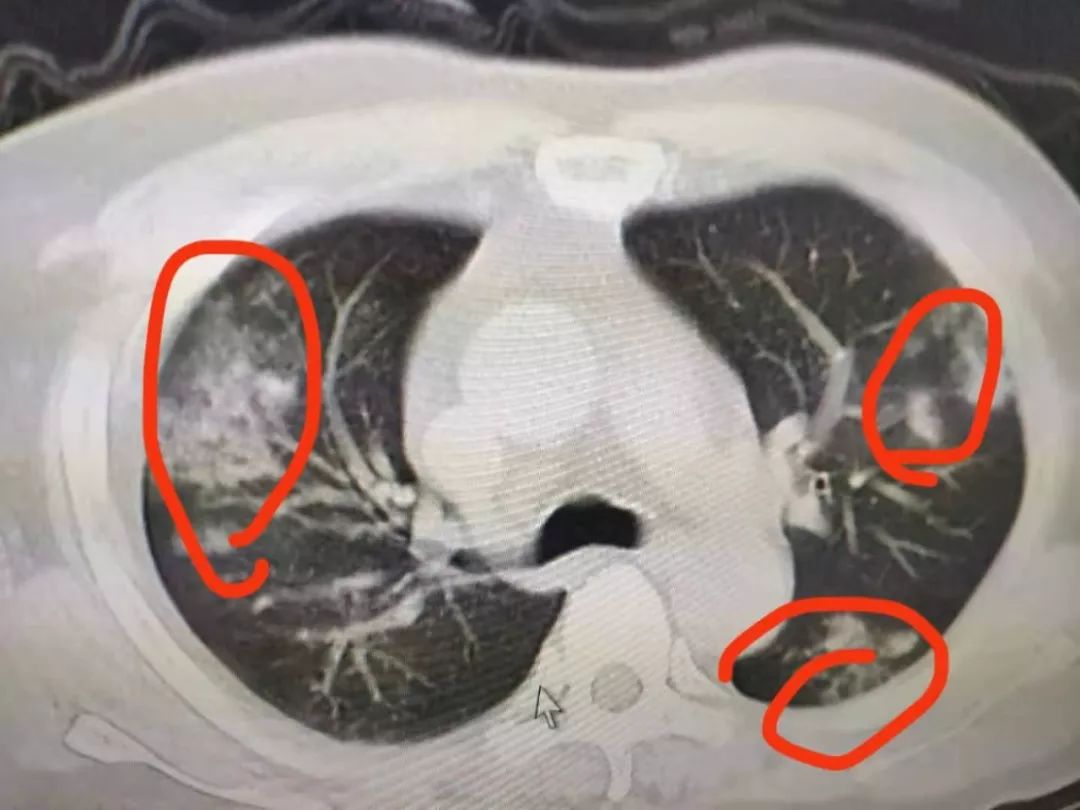

· 讲述者提供的病毒肺的 CT 图 -2- 科室与医院的现状 因为我们是心内科 , 现在属于二线科室了 。 封城前一个星期 , 我们医院就开始组织发热门诊、隔离病房 。 原来一个病房是三张床 , 可以放三个病人 。 隔离病房为了防止交叉感染 , 只能放一个病人 。 所以原来呼吸科的病人就转到我们这些二线科室去了 。 我们目前安排的班是一个人上 24 小时 , 然后休息 6 天 。 因为现在又开了几个呼吸内科 , 就抽调了好多医生去发热门诊和隔离病房 。 护士也抽掉了不少 , 去其他科室或者去支持金银潭这样的医院 。 非典的时候 , 因为大剂量使用激素治疗 , 很多病人治愈后留下了严重的后遗症 。 但这次到目前还没有看到有大剂量使用激素 。 如果高烧不退的话 , 会使用小剂量的 , 这个是正常范围之内的 。 我们临床都会用的 。 但是如果你的肺炎感染得很重 , 将来多多少少都会留下一点东西 。 就怕出现肺纤维化之类的情况 。 年轻的时候可能没什么 , 年老的时候就比较容易发生感染 。 目前武汉所有的医院 , 基本上都处于没有床位的状态 , 病人收不进去 , 除非你特别危重 。 像轻微和中度的病人 , 都是让他们回家自我隔离、吃药 , 这是没办法的事情 。 我现在看到一般门诊基本上没有什么病人了 , 以前大厅都是排满人的 , 现在就零零散散几个人 。 但是发热门诊人很多 , 排很长的队 。 而且晚上还比白天人多 , 可能他们怕小区的邻居知道自己来看病 。

· 封站前夕的火车站 , 工作人员在喷洒消毒剂 我当时还想着 , 大年二十九值完夜班之后就回家过年 , 初十之后再回来上班 , 但后面情况就越来越严重了 。 一月十几日我们这就出现了感染的情况 , 我们就开始自己买 N95 口罩、紫外线消毒灯、药品 , 这些都是自备 。 我那时候还觉得无所谓 。 真正慌的时候是 1 月 23 日武汉封城 , 没有想到这个病毒传播性这么强 。 我老家在武汉下面一个县城里 。 我就让老婆先回去了 , 我一直纠结自己回不回去 。 22 日抢口罩的时候 , 我本来说我要回去 , 我们主任说了一句 , 「你这不负责任 , 你在医院里面待过 , 你再回去就不怕传播给别人?」 这句话到后面我想了好几天 , 大年二十八我就跟科室说 , 我今年就不回家过年了 , 如果有任务可以安排我上 。 其实最终让我下定决心的 , 是我们同一批进来的一个同事 。 他当时去了发热门诊 , 然后告诉我 , 封城之前他在门诊看了 188 个病人 , 其中 88 个 CT 显示是阳性 , 所以封城前这个病情就比较严重了 。 所以我才决定不能回去 , 因为我多多少少也算暴露过几次 , 自己即使没有问题 , 不代表没有携带 。 还好封城之后 , 通过政府的宣传 , 现在大家都知道怎么回事了 。 现在 CT 阳性的话 , 我们只能叫疑似病例 。 因为确诊要用基因盒 , 这个我们非常紧缺 。 但是我们有一个标准 , 就是看 CT 是不是病毒肺 。 只要他 CT 上显示是病毒肺 , 这个人就应该八九不离十能确定感染了 。 这个病毒传染性非常强 , 我们科室目前有三、四个人在隔离病房 , 前两天基因检测后已经确诊了 。 因为我们有一个心内科去呼吸内科的会诊 , 不知道当时有没有接触到病人 , 可能去过那个病房就被感染了 。 后来我们就在科室里讨论了一下感染的主要症状 。 它不是看你有没有发热 , 或者流鼻涕、打喷嚏这些感冒的症状 。 它最先出现的症状是 , 我们看病人有没有乏力和有没有胃口 。 如果出现乏力、没有胃口 , 我们就建议去做个 CT , 确诊一下 。